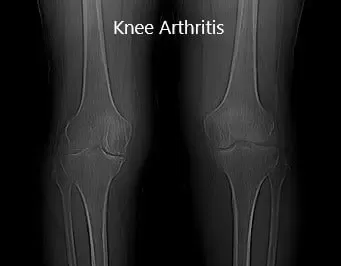

Las imágenes revelaron osteoartritis bilateral severa de rodilla. El paciente presentaba síntomas principalmente en la rodilla derecha, por lo que se le recomendó un reemplazo total personalizado. Se discutieron en detalle con el paciente los riesgos, beneficios y posibles complicaciones. Estaba muy motivado para volver a su estado habitual y optó por una artroplastia total personalizada.

Radiografía preoperatoria que muestra la vista panorámica de las articulaciones bilaterales de la rodilla.